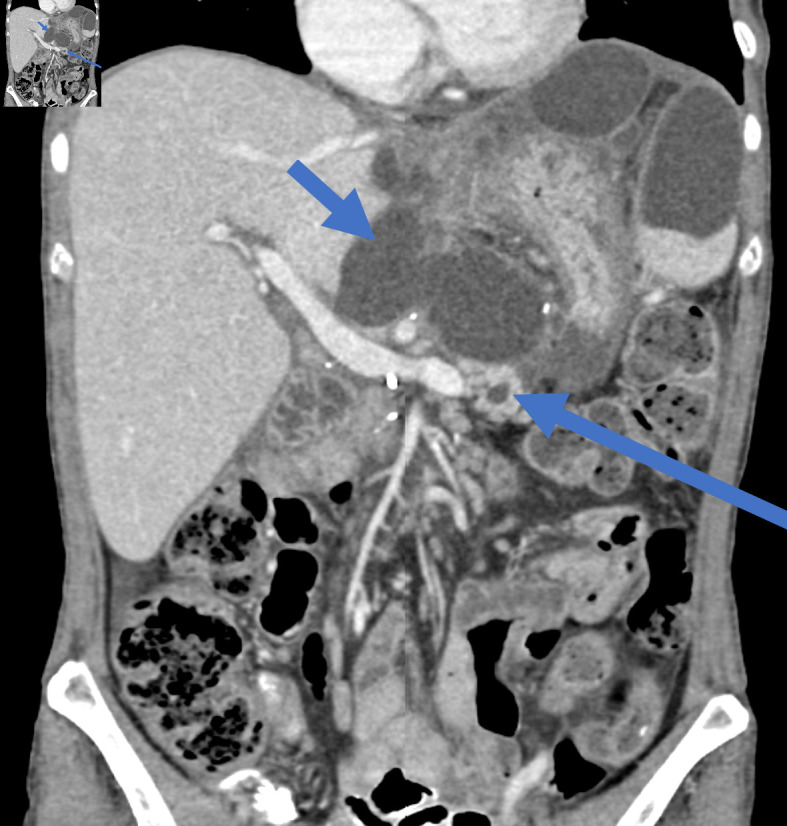

Pancreatoduodenectomy (PD) is a very complex and highly challenging operation for surgeons worldwide. It is the surgical procedure of choice for the management of benign and malignant diseases of the periampullary region. Although mortality rate following this complicated surgery has fallen to 1-3%, morbidity rate following PD remains high, with almost 30-40% of patients developing at least one complication. Postoperative pancreatic fistula (POPF) is one of the most common complications following PD. Therefore, Pancreatico-enteric anastomosis has been regarded as the "Achilles heel" of the modern, one-stage PD procedure. According to the International Study Group of Pancreatic Surgery (ISGPS), three types of POPF are recognized nowadays: biochemical leak, previously known as grade A POPF, grade B and grade C, with the latter being the most dangerous. Most POPFs, especially of the biochemical leak and grade B heal with non-operative management to recur later and present as an intra-abdominal abscess or pseudocyst, necessitating management by means of interventional radiology, endoscopy or surgery. These types of fistulas are undefined and occasionally intractable. Herein, we present two patients who presented with the aforementioned type of pancreatic fistula following duct occlusion PD. The first patient, a 53-year-old female patient, suffered from intolerance to oral feeding, severe weight loss and recurrent hospital admission, while the second patient, a 72-year-old patient, suffered from recurrent bouts of abdominal sepsis. Their management involved step-up approach, starting with non-operative management, followed by percutaneous drainage and operative treatment in the form of Puestow-like procedure (longitudinal pancreatojejunostomy), as a recourse due to the inadequacy of preceding therapeutic modalities.

Abstract Image